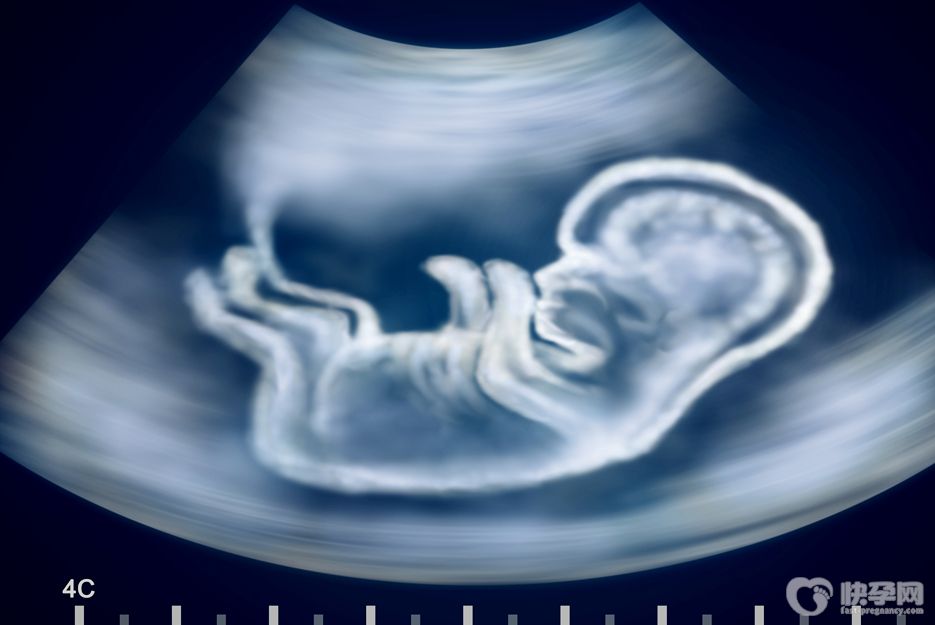

生一个聪明健康的宝宝是每一对夫妇所期望的事情,但对于艾滋病患者来说是不能通过自然受孕的方式获得健康的孩子。那么,艾滋病患者做供卵试管怀上的宝宝会被自己传染艾滋病呢?

母婴传播主要是孕妇在生产的过程中,由于皮肤黏膜的破损,产道中的体液或者血液中含有艾滋病毒,婴儿在生产的过程中可能会感染上艾滋病毒,因此女性生孩子时要阻断婴儿被传染,必须剖腹产,孩子出生后不能母乳喂养,只能人工喂养。

现阶段艾滋病母婴传播的发生率高达50%至60%,但只要你按照规范预防母婴传播流程管理,后期则可以完全预防母婴传播,从而生育健康宝宝。